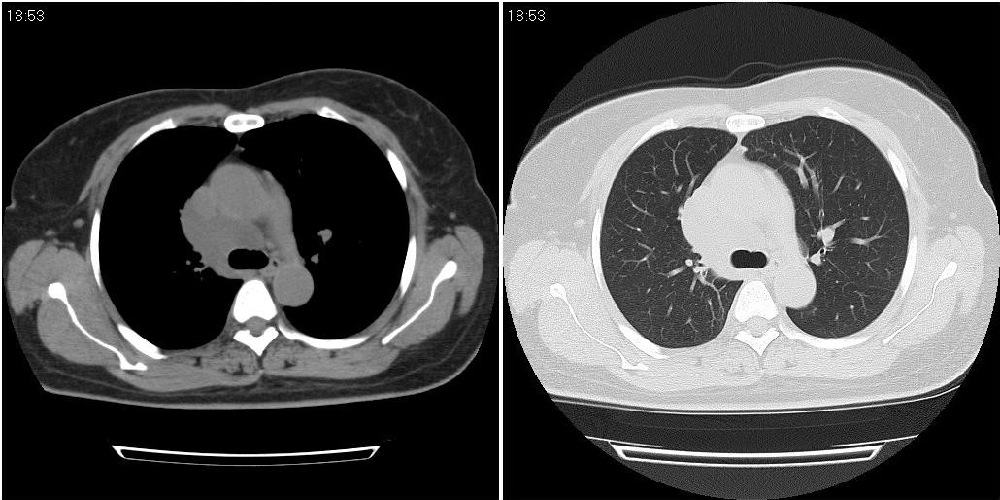

标题: CT24795:女性,47岁,右下腿静脉静脉曲张手术前体检,发现 [打印本页]

标题: CT24795:女性,47岁,右下腿静脉静脉曲张手术前体检,发现

囊性无明显占位效应:1淋巴管囊肿2畸胎瘤(其上部见小钙化)3前肠囊肿

右上纵隔囊性占位性病变;考虑淋巴管囊肿,不排除支气管囊肿。

支气管囊肿、囊性畸胎瘤、肠源性囊肿均有可能。

右上纵隔囊性占位性病变;考虑淋巴管囊肿,不排除支气管囊肿。 建议增强。

考虑淋巴管囊肿,不排除前肠囊肿。